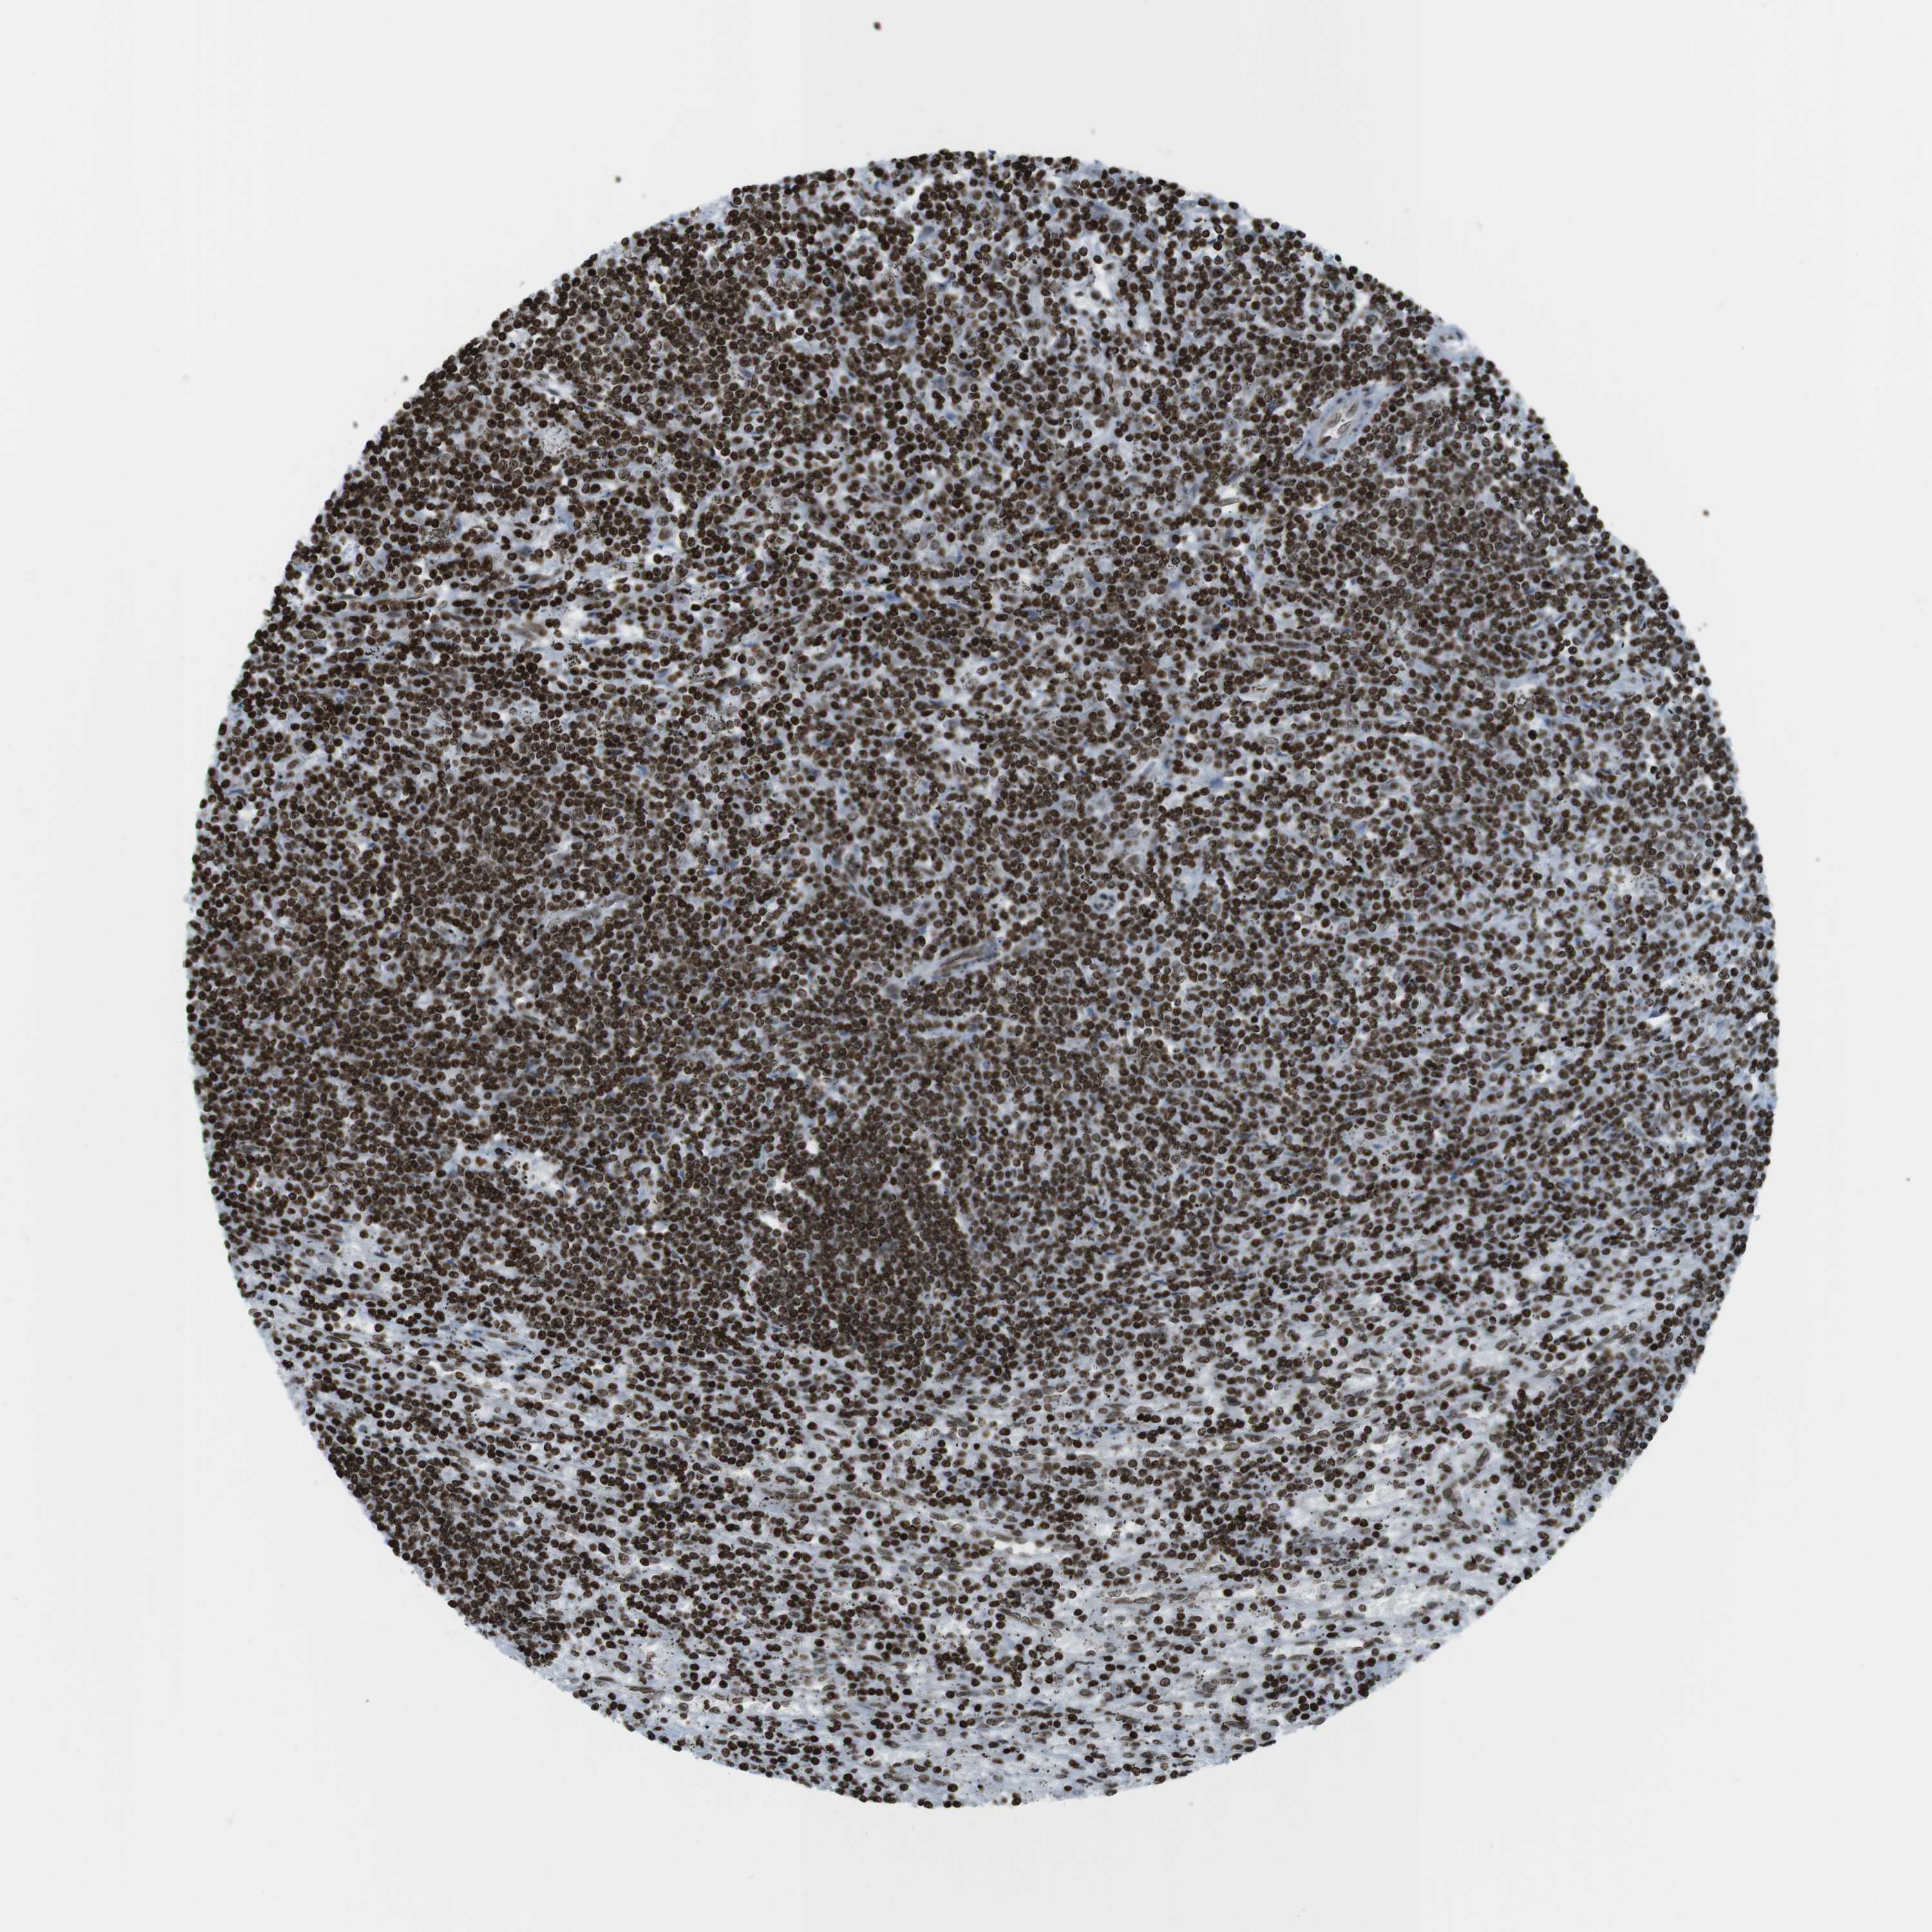

LYMPHOMA - Protein expressioni

A mouse-over function shows sample information and annotation data. Click on an image to view it in a full screen mode. Samples can be filtered based on level of antibody staining by selecting one or several of the following categories: high, medium, low and not detected. The assay and annotation is described here.

Each image is clickable and will lead to virtual microscopy that enables deeper exploration of all samples and also displays staining intensity scores, fraction scores and subcellular localization as well as patient and tissue information for each sample.

Antibody HPA041189

Antibody CAB012242

Staining

High

Medium

Low

Not detected

Intensity

Strong

Moderate

Weak

Negative

Quantity

>75%

75%-25%

<25%

None

Location

Nuclear

Cytoplasmic/membranous

Cytoplasmic/membranous,nuclear

Hodgkin's disease, NOS

Malignant lymphoma, non-Hodgkin's type, High grade

Malignant lymphoma, non-Hodgkin's type, Low grade